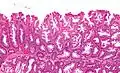

| Micrograph of a sessile serrated lesion. H&E stain. | |

SSLs are diagnosed by their microscopic appearance; histomorphologically, they are characterized by (1) basal dilation of the crypts, (2) basal crypt serration, (3) crypts that run horizontal to the basement membrane (horizontal crypts), and (4) crypt branching. The most common of these features is basal dilation of the crypts.

Unlike conventional colonic adenomas (e.g. tubular adenoma, villous adenoma), they do not (typically) have nuclear changes (nuclear hyperchromatism, nuclear crowding, elliptical/cigar-shaped nuclei).